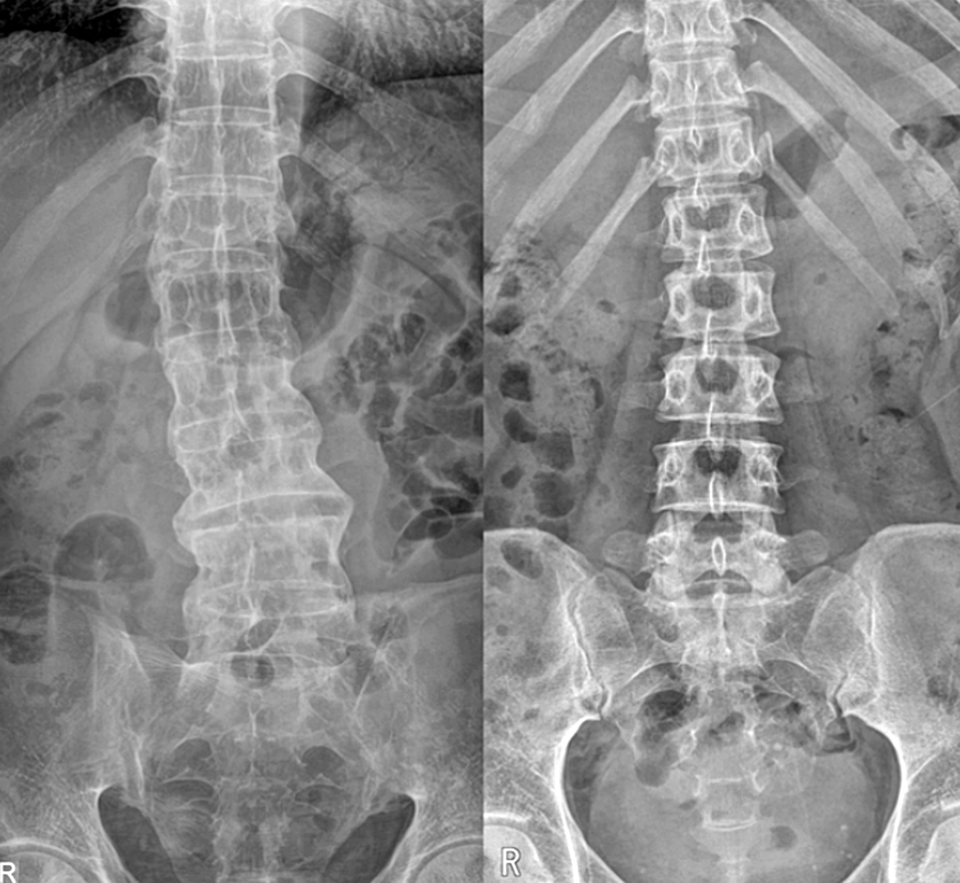

강직성 척추염은 척추와 천장관절 등에 만성 염증이 발생하는 자가면역질환으로, 조기에 치료하지 않으면 척추 뼈가 서로 붙어 움직임이 제한되고 일상생활에 큰 불편을 초래한다.

이 질환은 유전적 소인인 HLA-B27과 연관성이 있으며 허리 통증, 관절염, 부착부위염 등 근골격계 증상 외에도 눈·피부·위장관 등 전신에 영향을 미칠 수 있다. 대부분의 환자들이 호소하는 초기 증상은 아침에 허리 통증이 심하고 활동 후에는 증상이 호전되는 특징으로, 단순 근육통과는 양상이 다르다.

이주하 서울성모병원 류마티스내과 교수는 “강직성 척추염은 젊은 연령에서 시작해 사회생활과 일상에 큰 영향을 미칠 수 있는 질환”이라며 “척추 마디가 점차적으로 굳어가는 특성이 있는 만큼 조기 진단과 적절한 치료가 필수적이다. 증상이 반복된다면 지체하지 말고 전문의를 찾아 정확한 진단을 받아야 한다”고 강조했다.